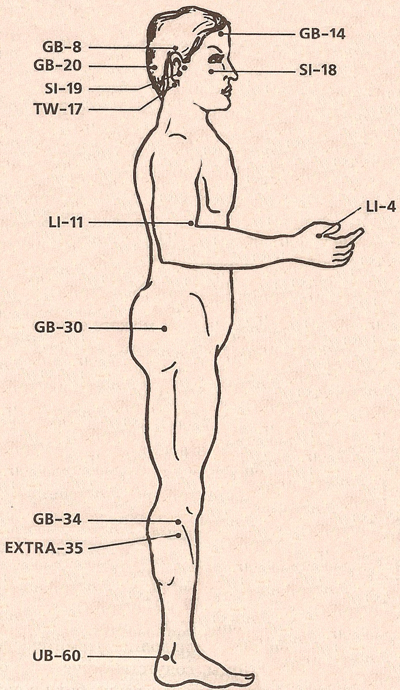

Исцеляющие точки нашего организма.

подробный атлас

Исцеляющие точки нашего организма.

подробный атлас

АКУПУНКТУРНЫЕ ТОЧКИ

АКУПУНКТУРНЫЕ ТОЧКИ

АКУПУНКТУРНЫЕ ТОЧКИ ПРИ ЛЕЧЕНИИ МАГНИТАМИ